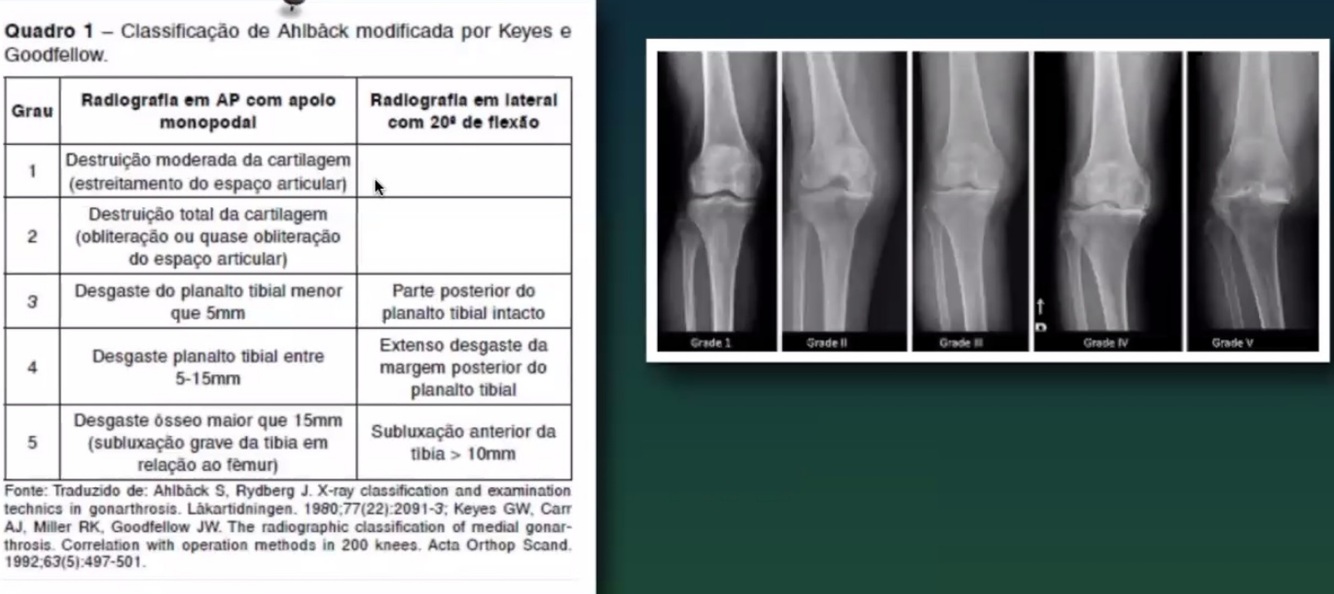

Classificação ahlback?

A

Gonartrose